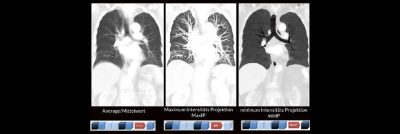

Categories: WebinarBildnachverarbeitung in der CT (Webinar | Online)

Alex Riemer Moderne CT-Scanner unterstützen die Anwenderinnen und Anwender bei der Durchführung der meisten CT-Untersuchungen. Hierzu zählt auch das automatische Erstellen von streng coronalen und sagittalen Multiplanaren Reformatierungen (MPR´s). Es gibt jedoch CT-Untersuchungen, bei denen die MPR´s individuell an die Anatomie angepasst werden müssen. Doch gerade bei diesen Bildnachverarbeitungen gibt es oft Unsicherheiten darüber, worauf es ankommt und wie sie […]